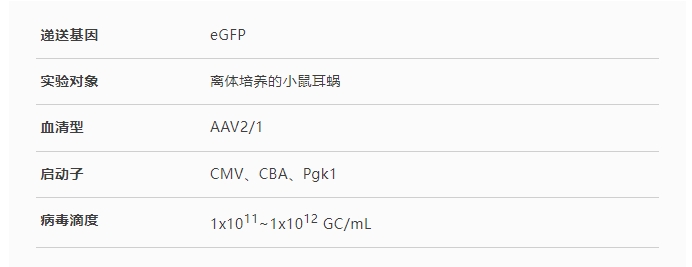

· 組成型啟動子

CMV和CBA已(yi)被證明可驅(qu)動(dong)耳蝸毛細(xi)胞(bao)(bao)、支(zhi)持細(xi)胞(bao)(bao)等(deng)多種細(xi)胞(bao)(bao)類型中的(de)轉基因表達(da)(da)����,Pgk1(磷酸(suan)甘油(you)酸(suan)激酶1)啟動(dong)子(zi)則可驅����(qu)動(dong)外源基因在支(zhi)持細(xi)胞(bao)(bao)中表達(da)(da)。

圖2. CMV、CBA和Pgk1啟動子驅動外(wai)源基(ji)因在離體培養小鼠耳蝸細胞中的表達

(Askew C, et al.Sci Transl Med.2015)